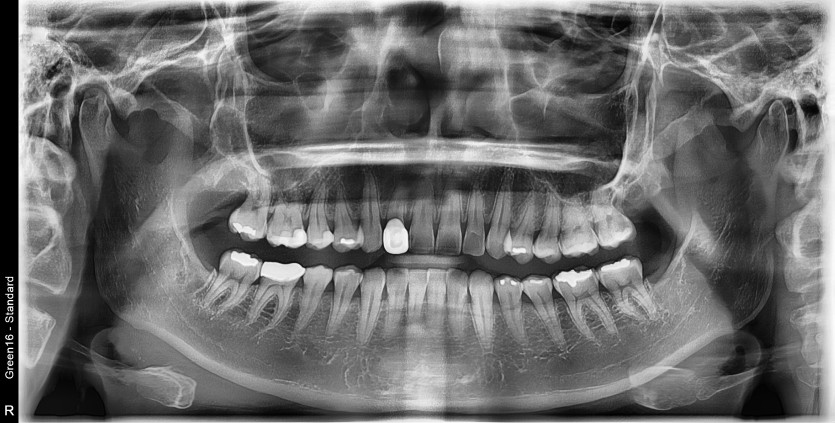

#18,28,38,48 사랑니 발치

구강 외과 전문의가 당일 발치했습니다.